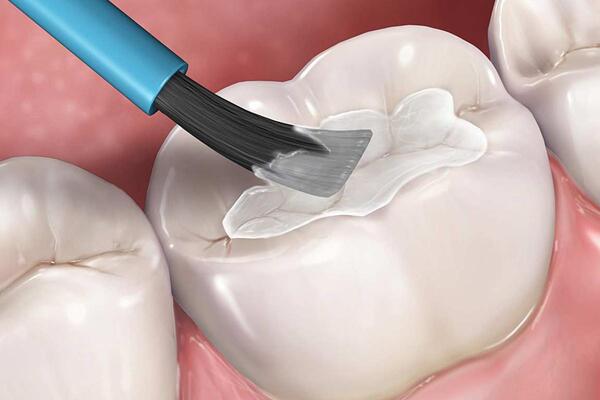

Trám bít hố rãnh để ngăn sâu răng

Trám hố rãnh là phương pháp nha khoa giúp ngăn sâu răng ở những vị trí khó làm sạch, đặc biệt là răng hàm và răng cối. Khi trám, vật liệu như composite, amalgam hoặc sứ sẽ tạo một lớp phủ chắc chắn, bảo vệ men răng khỏi vi khuẩn và hỗ trợ quá trình tái khoáng tự nhiên.

Thực hiện trám đúng kỹ thuật và kiểm tra răng định kỳ giúp phát hiện sớm vết sâu nhỏ để điều trị kịp thời, tiết kiệm chi phí và tránh biến chứng. Đây là biện pháp phòng ngừa hiệu quả, giúp men răng luôn bền chắc và duy trì sức khỏe răng miệng lâu dài.

Trám răng thẩm mỹ khi mòn men

Khi men răng bị mòn hoặc hư hại nặng, trám răng thẩm mỹ là giải pháp giúp khôi phục hình dạng, màu sắc và chức năng ăn nhai. Vật liệu như composite hoặc sứ có độ bền cao, phù hợp với từng tình trạng răng, đồng thời mang lại hiệu quả thẩm mỹ tự nhiên.

Việc trám răng còn giúp ngăn vi khuẩn xâm nhập sâu vào mô răng và tạo bề mặt răng sáng đẹp như thật. Quy trình nhanh, ít đau và an toàn, nhưng cần được thực hiện tại nha khoa uy tín với bác sĩ giỏi và vật liệu chất lượng để đảm bảo kết quả bền đẹp và bảo vệ men răng tối ưu.